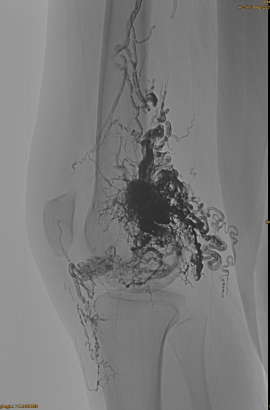

Patsiendi põhiteave: naine, 36 aastat; AVM vaavis, puusa, põlv, vasakul OSG, mitu pre - emboliseerimist.

Esialgne DSA:

Lõpptulemus:

Vaevalt ükski venoosne väljavool: